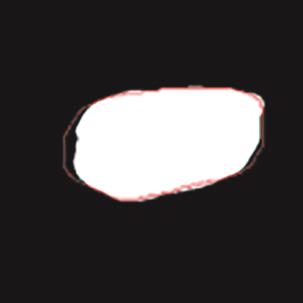

乳腺癌是全球女性最常见的恶性肿瘤之一,准确的病变分割对于乳腺癌的早期诊断与治疗具有重要意义。然而,由于病变形态的多样性以及超声成像机制的复杂性,现有基于深度学习的乳腺超声图像病变分割方法在分割准确性方面仍面临巨大挑战。为进一步提升乳腺超声图像中病变区域的分割精度,该文基于经典U-Net架构,提出了一种新型乳腺超声图像病变分割网络(CWSASKM-BBAM-Net)。首先,在网络中引入逐通道空间自适应选择核卷积模块(CWSASKM),根据不同通道的语义特征为每个空间位置自适应选择感受野大小,以增强多尺度信息的建模能力;然后,引入双向边界感知机制(BBAM),通过融合正向与反向注意力,对目标显著区域及其边界进行协同建模,同时逐步提升对非显著区域与病变区域的区分能力,以进一步强化边界信息的表达;最后,在3组公开乳腺超声图像数据集(BUSI、UDIAT和STU)上开展分割实验。结果表明:该方法在数据集BUSI上的杰卡德指数、精确率、召回率和Dice相似系数分别为71.97%、82.85%、81.40%和80.44%,较次优方法分别提升1.69、1.05、1.28和1.84个百分点;在数据集UDIAT上,这4项指标分别达到78.14%、88.31%、86.73%和86.10%,较次优方法分别提升了2.75、2.04、0.56和2.01个百分点;在外部数据集STU上,该方法也取得了优于其他方法的整体表现。实验结果表明,CWSASKM-BBAM-Net在乳腺超声图像分割任务中展现出更优的整体性能。